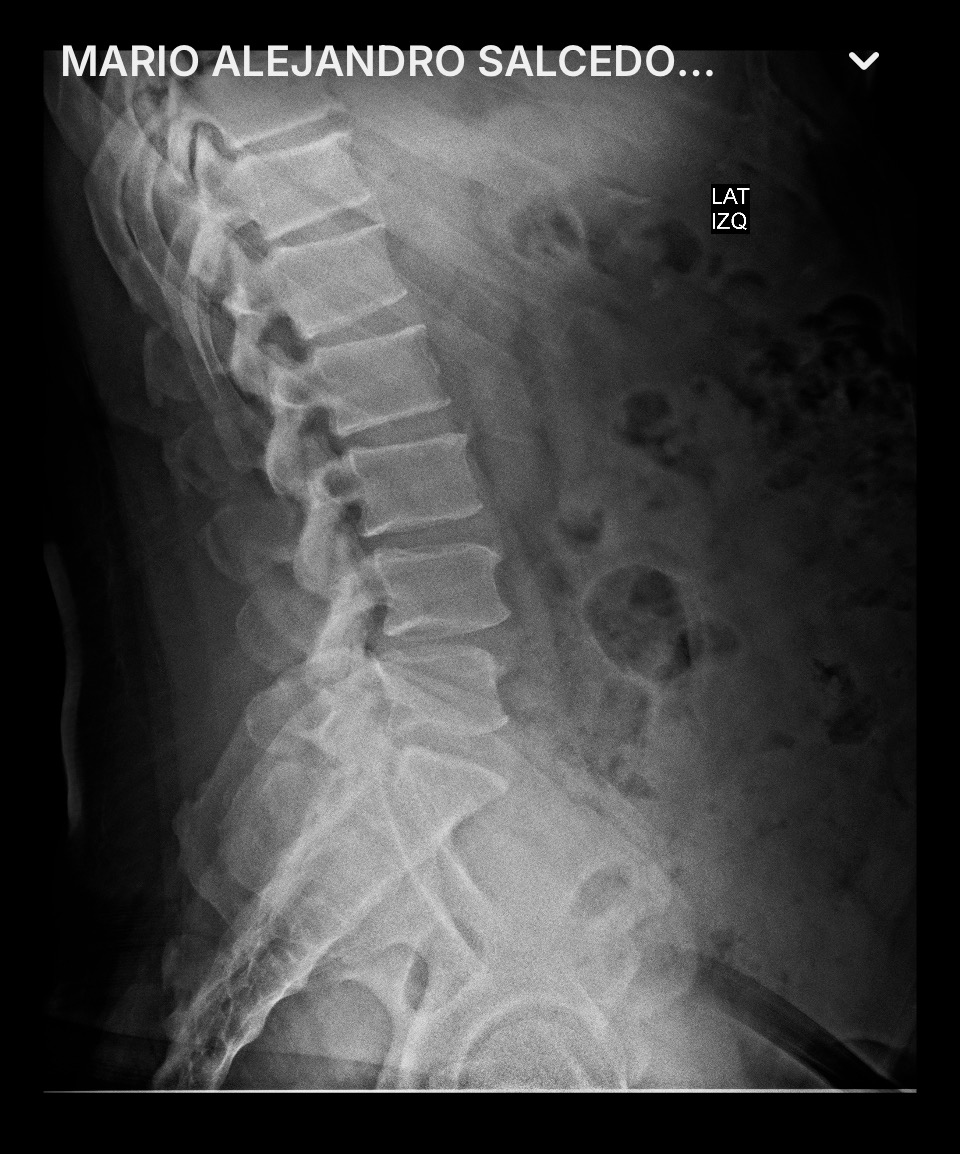

El día martes, 4 de noviembre de 2025, fuimos a ver a un nuevo doctor neurocirujano, que me envió de carácter urgente a realizarme nuevos estudios (RX's y resonancias magnéticas), así como también análisis de sangre y orina.

Este doctor neurocirujano me comentó que ya estaba en una situación de carácter urgente y que tenía que ser intervenido quirúrgicamente, ya que mi médula espinal está comprometida, diciéndome, en otras palabras, que en cualquier momento puedo quedar sentado. Pero que si me opero en este momento, tendría una esperanza para poder recuperarme y disfrutar de una vida normal acompañado de mi esposa e hijas.